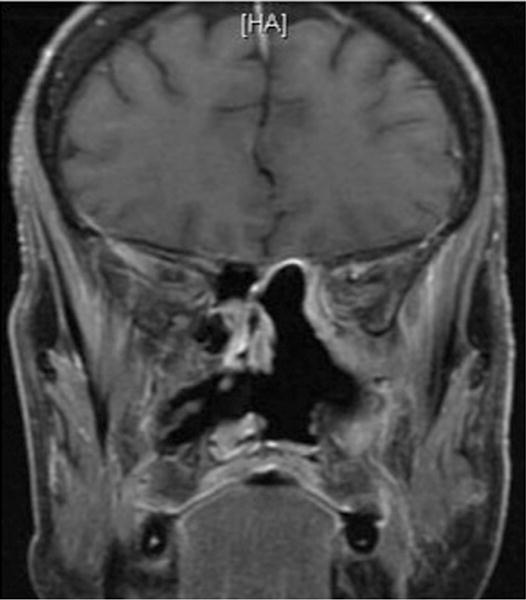

Fig. 6.

Patient 3. Postoperative coronal T1-weighted post-contrast MRI demonstrating complete resection of the sinonasal melanoma.